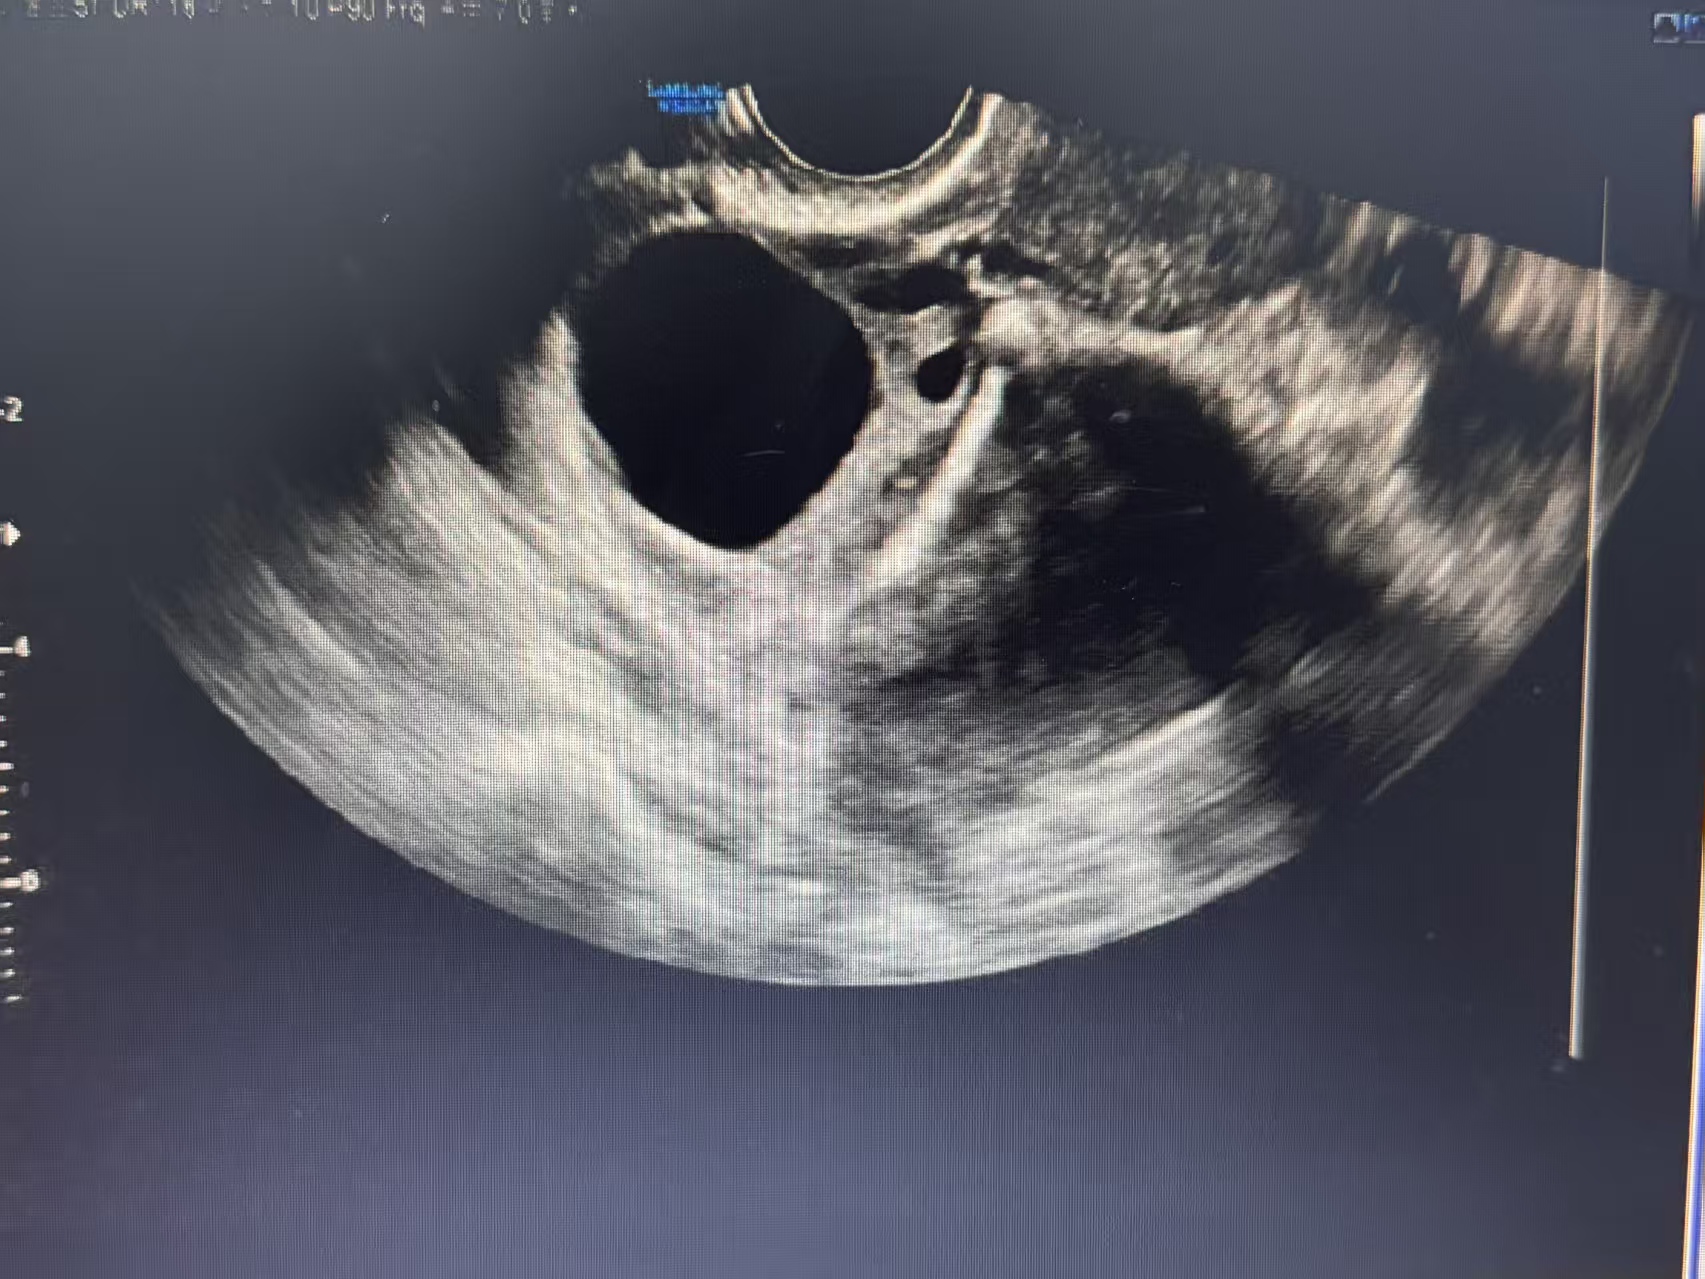

超声检查无辐射、无创、实时,能清晰显示囊肿的位置、大小、形态、内部结构和血流情况,宛如一位敏锐的侦探,为我们提供第一手证据。经阴道超声分辨率更高,是观察卵巢细节的利器。

1. 形态与大小:报告常描述为“无回声区”,对其大小进行测量,常见的囊肿呈圆形或椭圆形。

清澈如泉(无回声):常为单纯性囊肿,良性可能性大。